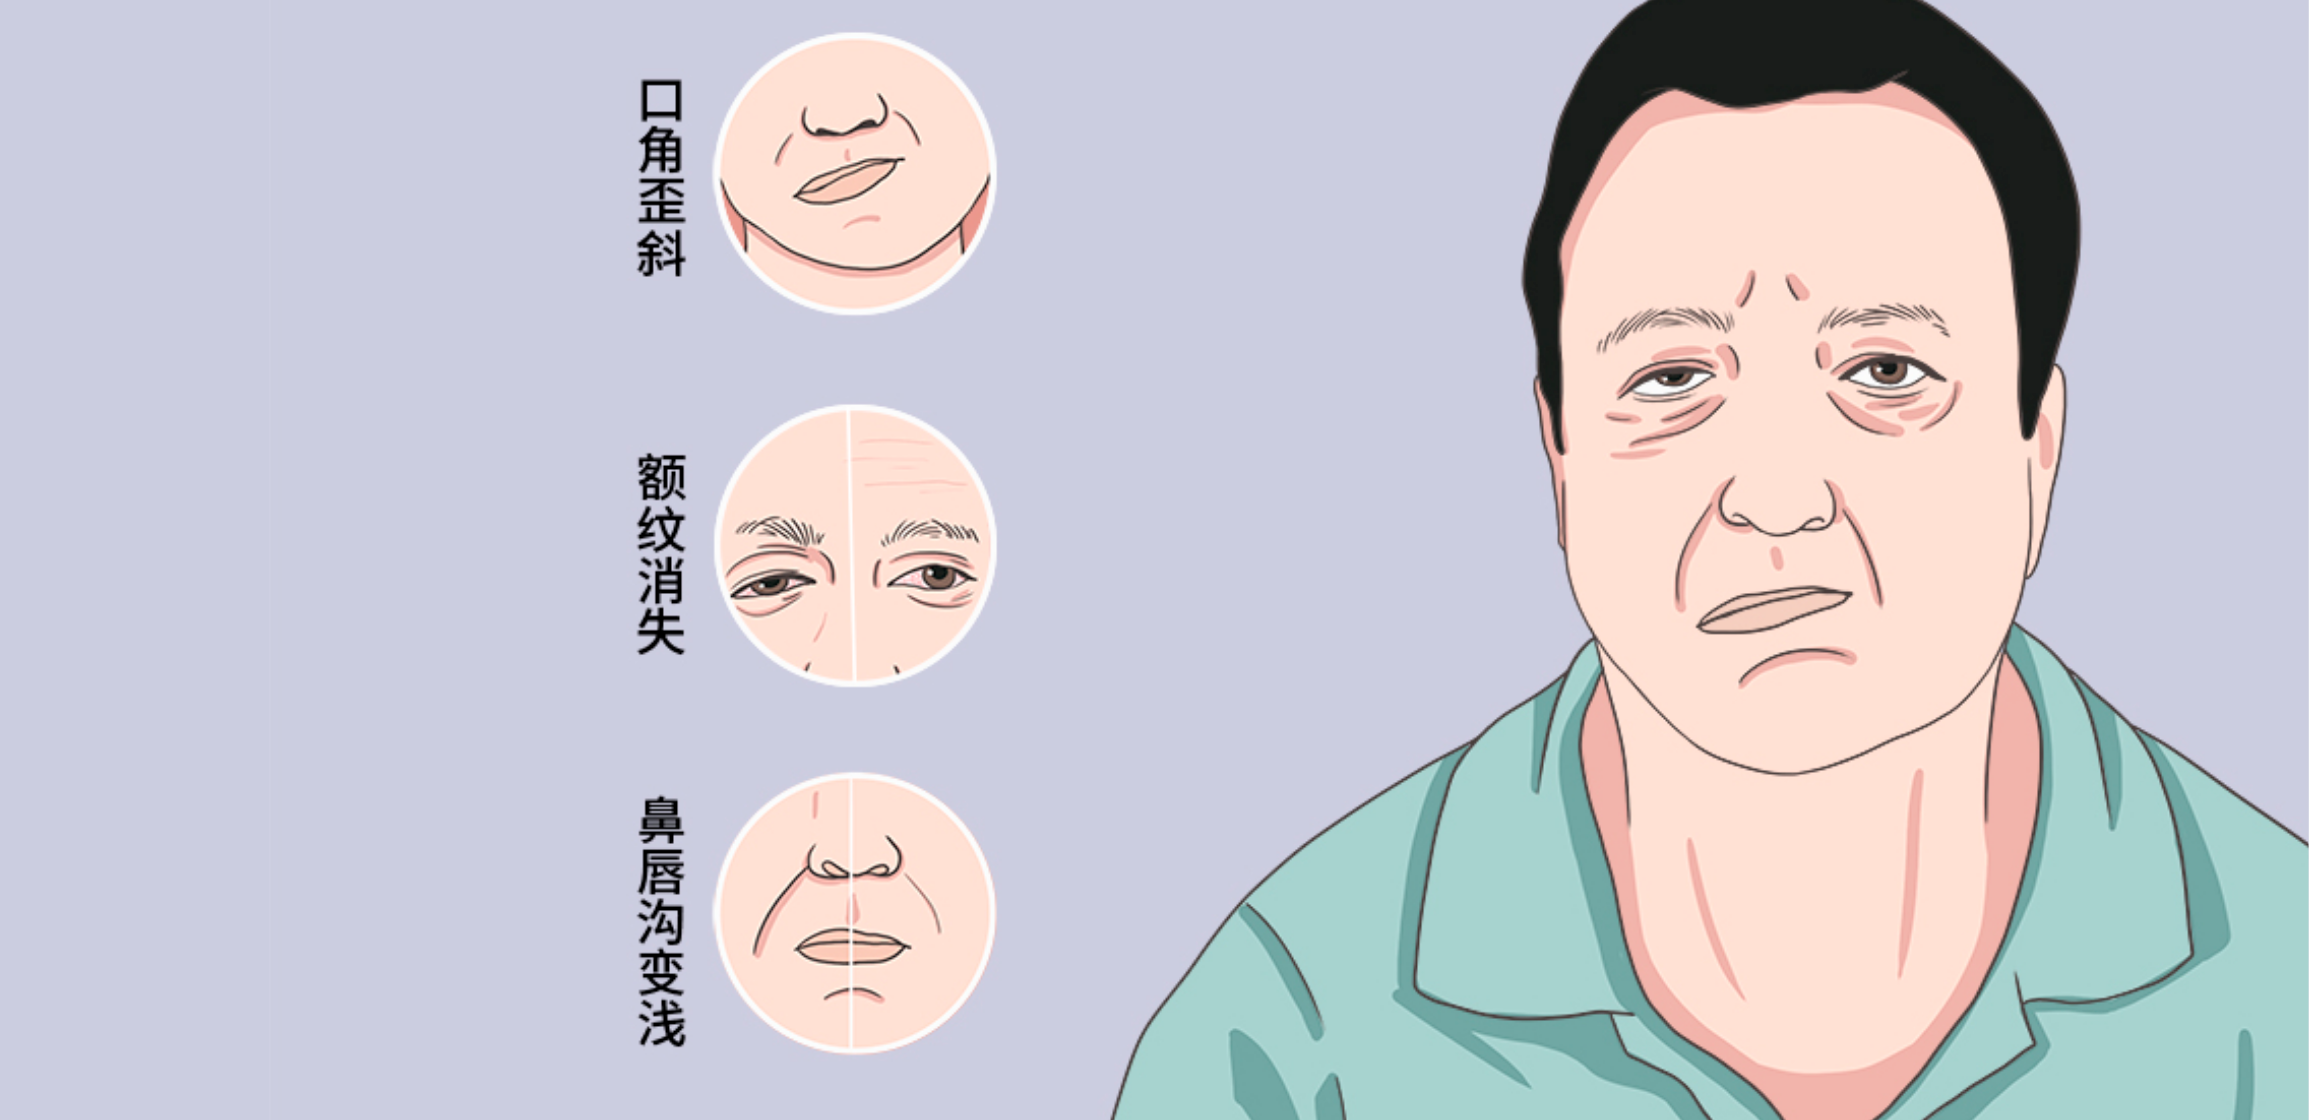

面瘫

FACIAL PARALYSIS

在口腔医学语境中,面瘫(面神经麻痹) 指面神经受损导致的面部表情肌运动功能障碍,核心表现为单侧 / 双侧面部肌肉无力、瘫痪(如嘴角歪斜、无法闭眼、鼓腮漏气),口腔领域多关注与口腔诊疗相关的诱因及并发症处理。